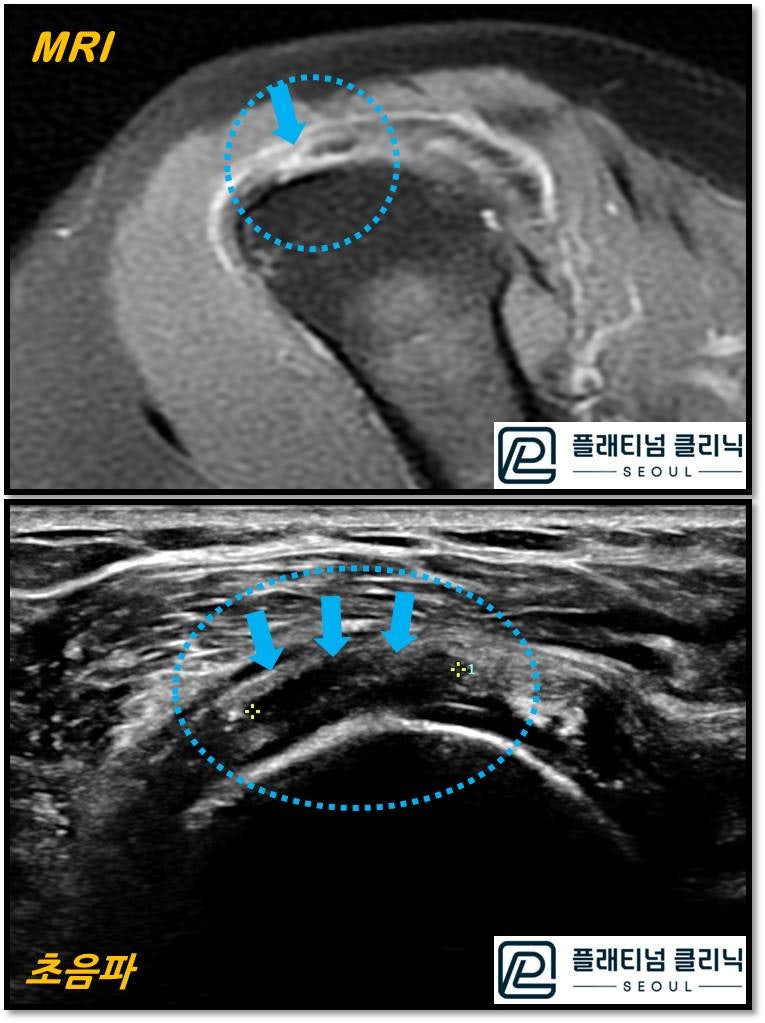

같은 환자 회전근개 파열에서 단면을 자른 영상을 비교한 것입니다. 한눈에 봐도 초음파가 더 크고 선명하게 보이지 않으신가요? 파열된 부위가 훨씬 선명하게 잘 보입니다. 이것 뿐 아니라 초음파는 연속적으로 검사를 하기 때문에 미세한 석회나 염증, 파열등을 MRI 보다 더 잘 진단할 수 있습니다. MRI 에서는 파열이 큰 경우나 석회가 큰경우(4mm 이상) 진단이 되나 그 이하에서는 진단이 어렵습니다. 물론 초음파를 보는 술자에 따라 차이는 있을 수 있습니다. 경험이 많은 정형외과 의사라면 충분히 MRI 없이 회전근개 질환의 진단을 초음파로 할 수 있습니다.